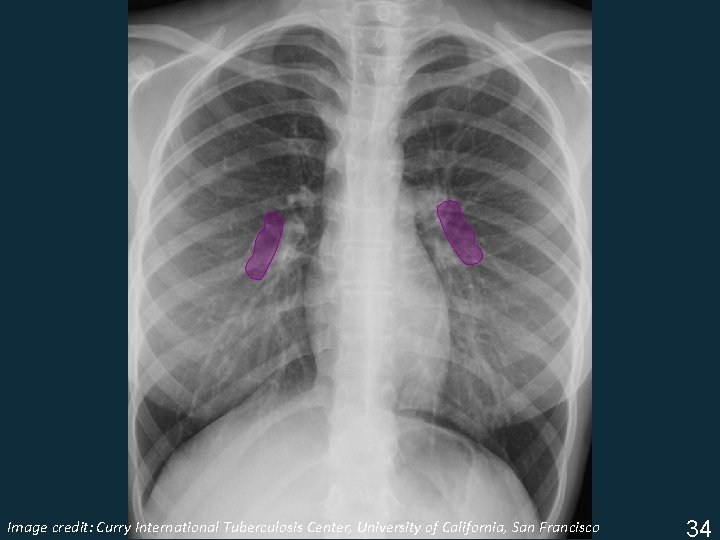

Image Tuberculosis Center, University of California, San Francisco ISTC TBcredit: Training Curry Modules. International 2009 34

Lymphadenopathy § Infrahilar window (right hilar and/or subcarinal) § Left hilar § Subcarinal Image Tuberculosis Center, University of California, San Francisco ISTC TBcredit: Training Curry Modules. International 2009 35

Lymphadenopathy § Infrahilar window (right hilar and/or subcarinal) Image Tuberculosis Center, University of California, San Francisco ISTC TBcredit: Training Curry Modules. International 2009 35

Lymphadenopathy § Left hilar Image Tuberculosis Center, University of California, San Francisco ISTC TBcredit: Training Curry Modules. International 2009 35

Lymphadenopathy § Subcarinal Image Tuberculosis Center, University of California, San Francisco ISTC TBcredit: Training Curry Modules. International 2009 35